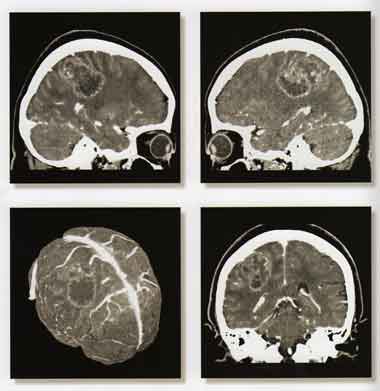

Объёмное образование головного мозга.

Все вышеизложенные методы диагностики проводятся с помощью Мультисрезового спирального компьютерного томографа Toshiba (Asteion Super 4) - 26 декабря 2006 года выпуска, который находится на базе 19-й городской больницы.

Аппарат Toshiba Astieon Super 4: относится к системе 3 поколения с непрерывным оборотом трубки и наиболее подходит для исследования головного мозга и всего тела включая исследования сердечно – сосудистой системы. Многосрезовая технология системы Asteion позволяет получать действительно изотропные объёмные данные. Эта технология позволяет расширить применение КТ и значительно увеличивает диапазон исследований.

Высокое качество изображения и низкая лучевая нагрузка получается за счет эффективного использования дозовой нагрузки.